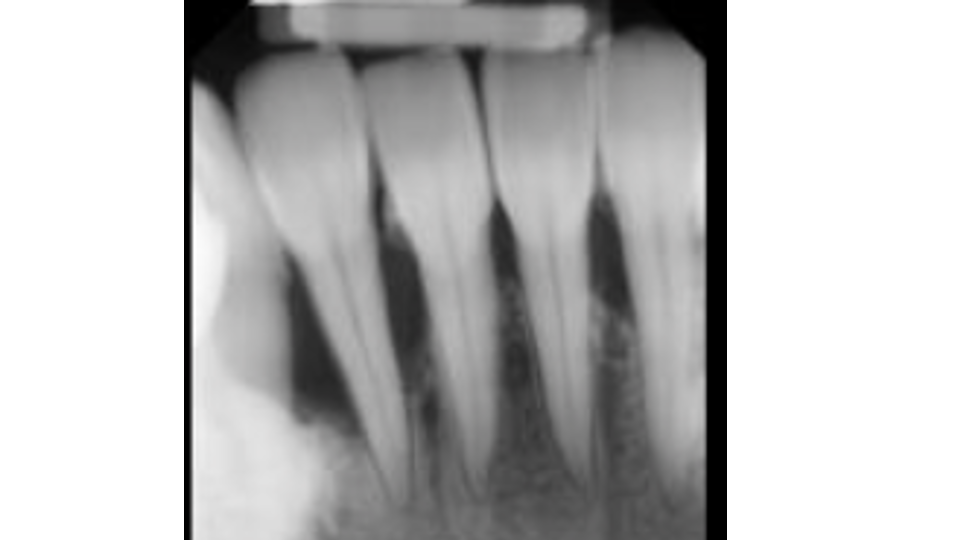

This patient is lacking all keratinized tissue. They only have thin alveolar mucosa surrounding their teeth which is leading to both recession and bone loss.

- Ongoing bone loss: Bacteria that migrate down an unsealed root surface can reach the bone supporting your tooth. When that happens, your body's inflammatory response actually resorbs (destroys) the bone to try to maintain distance from the bacteria. This creates a cycle: bone loss exposes more root, which allows more bacteria, which causes more bone loss.

Take a closer look at the difference between the two areas in this patient's mouth. The teeth surrounded by thick, firmly attached protective tissue show no plaque buildup, no inflammation, and stable, healthy gum levels. In contrast, the sites that lack this protective tissue are visibly inflamed and collecting bacteria along the gumline, which is driving progressive recession. Without intervention to rebuild that protective barrier through grafting, the affected teeth would continue to lose gum tissue and bone support over time, ultimately putting them at risk of being lost entirely.